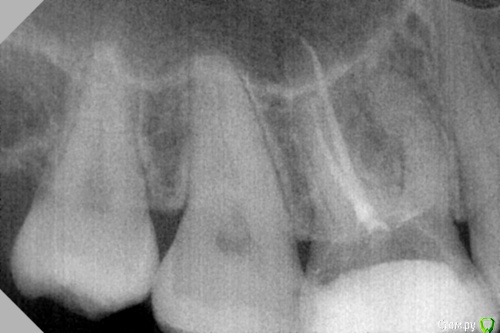

dr.Dre Опубликовано 23 июня, 2017 Поделиться Опубликовано 23 июня, 2017 Добрый день коллеги ,16 зуб долго мучался так и не нашел вход в канал, работал под микроскопом поделитесь опытом как выйти из ситуации ? Ссылка на комментарий

vse32 Опубликовано 23 июня, 2017 Поделиться Опубликовано 23 июня, 2017 Если верить контурам на снимке, то, возможно, не там ищите. Сместитесь чуть центральнее. А может и чуть глубже копнуть нужно. Ссылка на комментарий

parallax Опубликовано 23 июня, 2017 Поделиться Опубликовано 23 июня, 2017 Мне кажется, нужно сместиться чуть медиальнее. И да, чуть глубже. Ссылка на комментарий

Паращук Роман Опубликовано 24 июня, 2017 Поделиться Опубликовано 24 июня, 2017 протравить,смыть,искать разницу цветов,красить маркером,залить хлорку-искать бульбашки.ПиСи: очень много вопросов по энло у Вас.В Виннице суперский центр по обучению. По эндо отличный состав лекторов и главное все на маникенах/людях и в скоп. Вам стоит туда поехать. Ссылка на комментарий